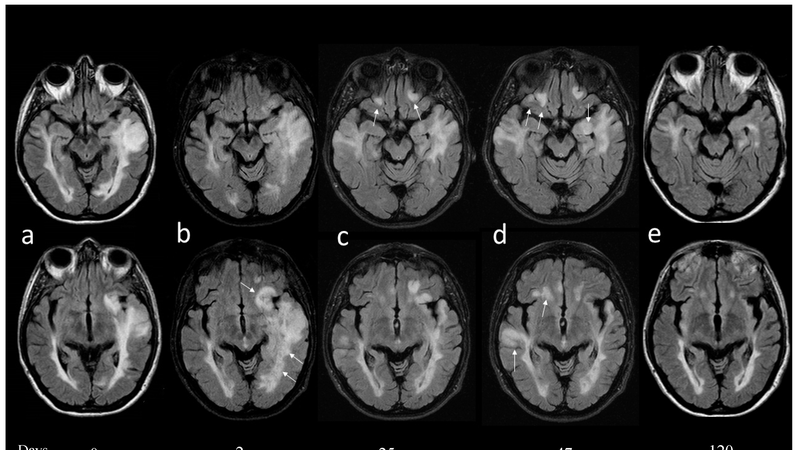

Đặc điểm của ADEM là các thiếu sót thần kinh cùng với những tổn thương mất myelin ở nhiều vị trí khác nhau trên phim chụp cộng hưởng từ (MRI) sọ não và tủy sống. Về mặt bệnh học, bệnh biểu hiện bằng viêm các tế bào quanh mạch máu nhỏ, chủ yếu là các tế bào thần kinh đệm, cùng với sự mất myelin.